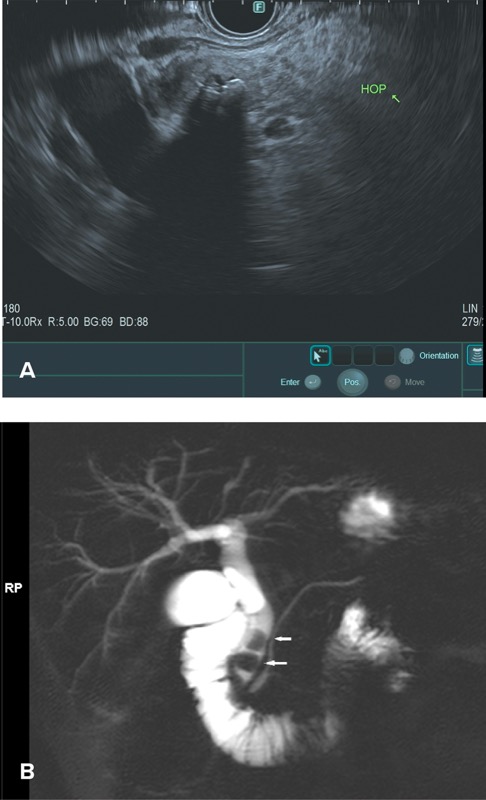

Occult biliary disease has been implicated as a common cause of IAP, with the mechanism being transient obstruction at the ampulla of Vater. Microlithiasis (stones <3 mm in diameter) and biliary sludge—a suspension of crystals (cholesterol monohydrate, calcium bilirubinate, or calcium carbonate), mucin, glycoproteins, cellular debris, and proteinaceous material within bile—can be found within the gallbladder or bile ducts and may be missed by standard imaging. Prospective studies have found that approximately one-fifth to three-fourths of patients with presumed IAP have sludge or stones in the gallbladder, 34,35 with diagnosis based on microscopic examination of bile for crystals and usually confirmed on evaluation of the resected gallbladder or follow-up gallbladder ultrasound showing gallstones and/or sludge.

In the past, at the time of ERCP, it was recommended that bile be collected from the duodenum or bile duct after gallbladder stimulation with cholecystokinin or by direct cannulation of the gallbladder.36,37 Today, however, ERCP rarely is performed specifically for bile crystal analysis, given the risk for post-ERCP pancreatitis and the high sensitivity of EUS in detecting biliary sludge and microlithiasis (Figures 2 and 3A). Furthermore, TUS technology also has advanced significantly, with improved detection rates.

In a large meta-analysis, EUS was found to have a significant benefit in detecting occult biliary disease compared with MRCP (Figure 3B) in IAP.29 Ardengh et al found gallbladder microlithiasis in 27 of 36 patients with IAP using EUS (75%).38 When compared with the final surgical resection specimen, the sensitivity and specificity for EUS identification of gallbladder microlithiasis were 92.6% and 56%, respectively. The overall EUS accuracy in this study was 83.2%.

MRCP and S-MRCP are usually the diagnostic modalities of choice for PD, given their noninvasiveness (Figure 4). Studies have demonstrated the high diagnostic accuracy of S-MRCP.65-67 Mosler et al found that S-MRCP had an overall sensitivity and specificity of 73% and 97%, respectively, when compared with ERCP in 19 patients.65 The sensitivity and specificity improved to 83% and 99% in the subgroup of patients without CP. A meta-analysis and systematic review of 11 studies evaluating the utility of MRCP, S-MRCP, and EUS found similar results, with specificities of 99% for both MRCP and S-MRCP but a higher sensitivity of S-MRCP (83% vs 59%).66 Data also suggest that S-MRCP could help identify a subgroup of patients who might respond to endoscopic therapy, as evidenced by a recently published retrospective study from 3 tertiary centers in China evaluating 120 patients with PD who underwent endoscopic retrograde pancreatography.67 The investigators found that linear array EUS had a sensitivity of 90.8%, a specificity of 99.8%, and an overall diagnostic accuracy of 99%, suggesting it is a reasonable alternative to S-MRCP. They also noted that the degree of duct dilation suggested an obstructive process and might correlate with or predict a response to minor papilla intervention, but this assumption has not been proven conclusively to date.